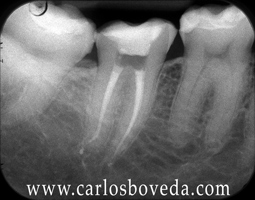

(para ver las rx a mayor tamaño haga click sobre ellas)